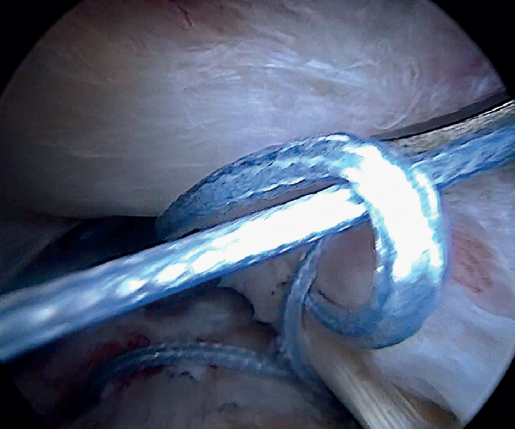

Using penetrating forceps through the anterior portal, the surgeon penetrates the LPB and retrieves one of the suture threads, performing a self-locking Lasso suture in the same step. This is done with two of the three anchoring threads to ensure a correct LPB grip to the footprint of the greater tuberosity and that the tendon does not fray; we do not cut the two threads after knotting (Figures 4, 5 and 6). We also consider it very important to apply the biceps tendon, keeping it as flat and anatomical as possible, avoiding twisting or excessive distension of the tendon. Subsequently, a tenotomy of the LPB distal to these sutures is performed (Figure 7), thus allowing the LPB to function as a superior capsular reconstruction, restricting the ascent of the humeral head.